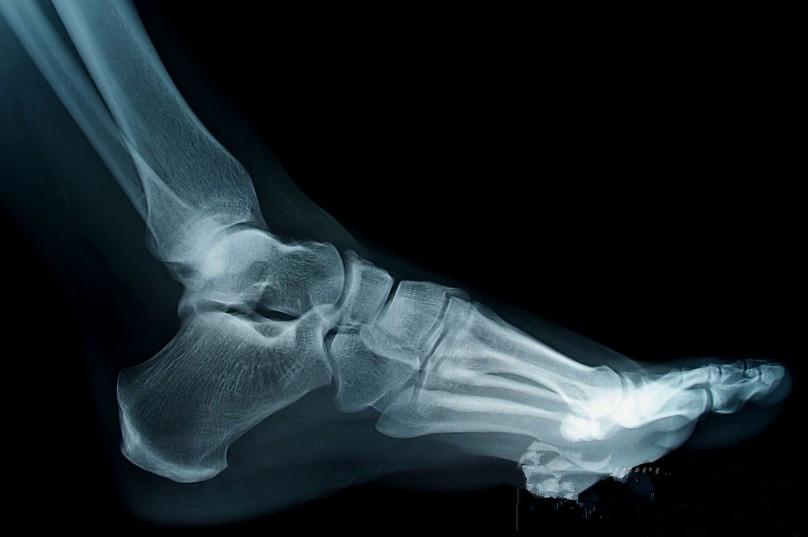

人的足弓在出生后两岁开始发展,而成长到十岁后成形,若足弓在成年后仍扁平的话则称为成年扁平足(flat foot)。成年人约有15%的比例有此情形,而其中多数为功能性扁平足。在理学检查上在站立承重时可见足弓内侧塌陷,而在坐姿下或是垫脚尖站立时可再次看见足弓。